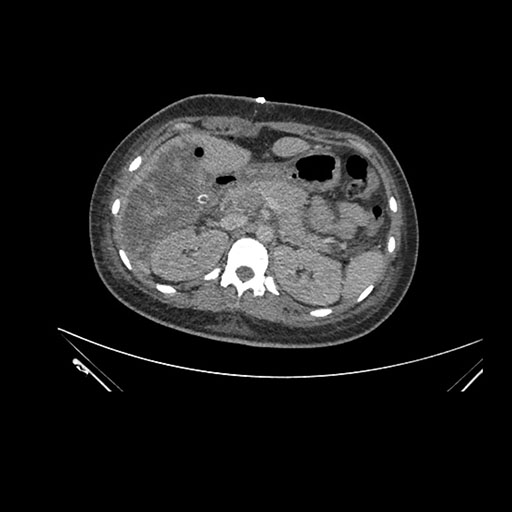

Imaging Analysis

Look through the patient's CT scan to identify any areas of concern for the necessary procedure.

Axial Venous